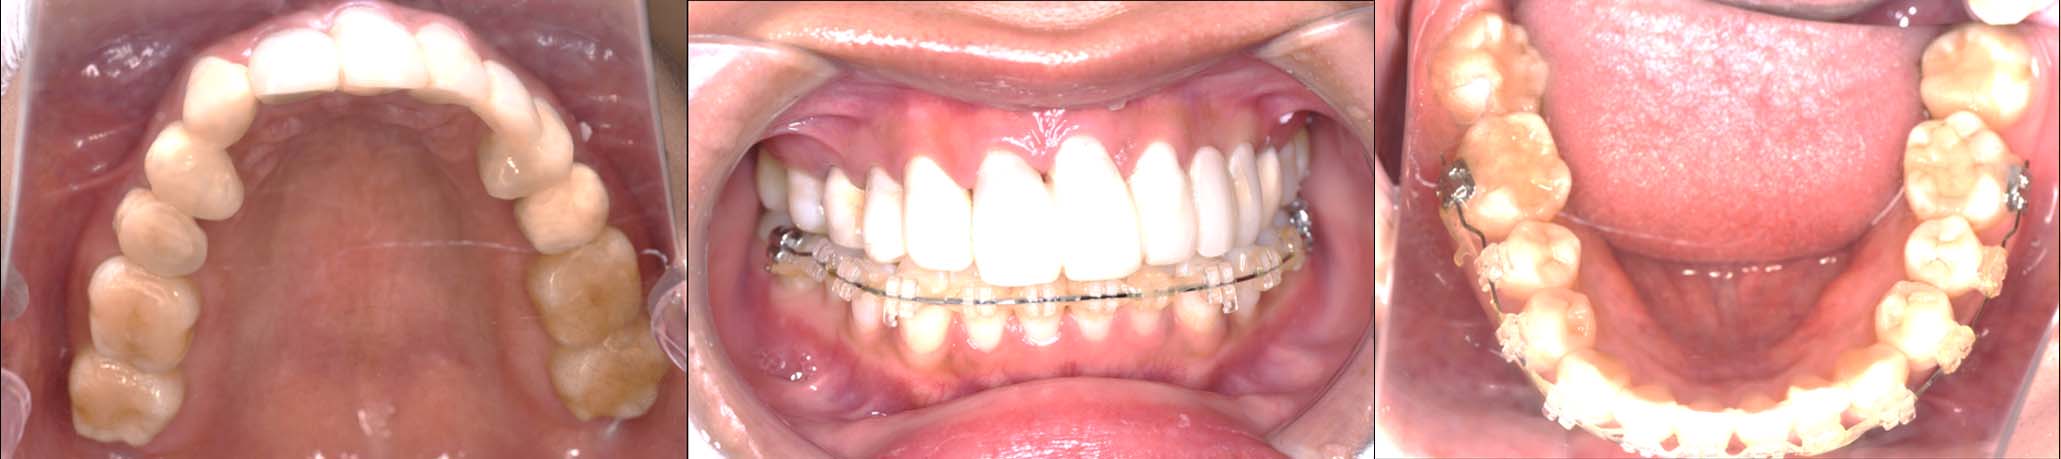

| 治療内容 | ①スプリントを装着 ②副子を装着 ③2024年4月 口腔内反映開始 ④副子を入れた状態の所まで咬合を挙上 (バイトアップ) ⑤2024年5月 上顎前歯部8本に仮歯(TEK) を装着 |

2024年 10月 下顎MTM開始

2024年 10月10日